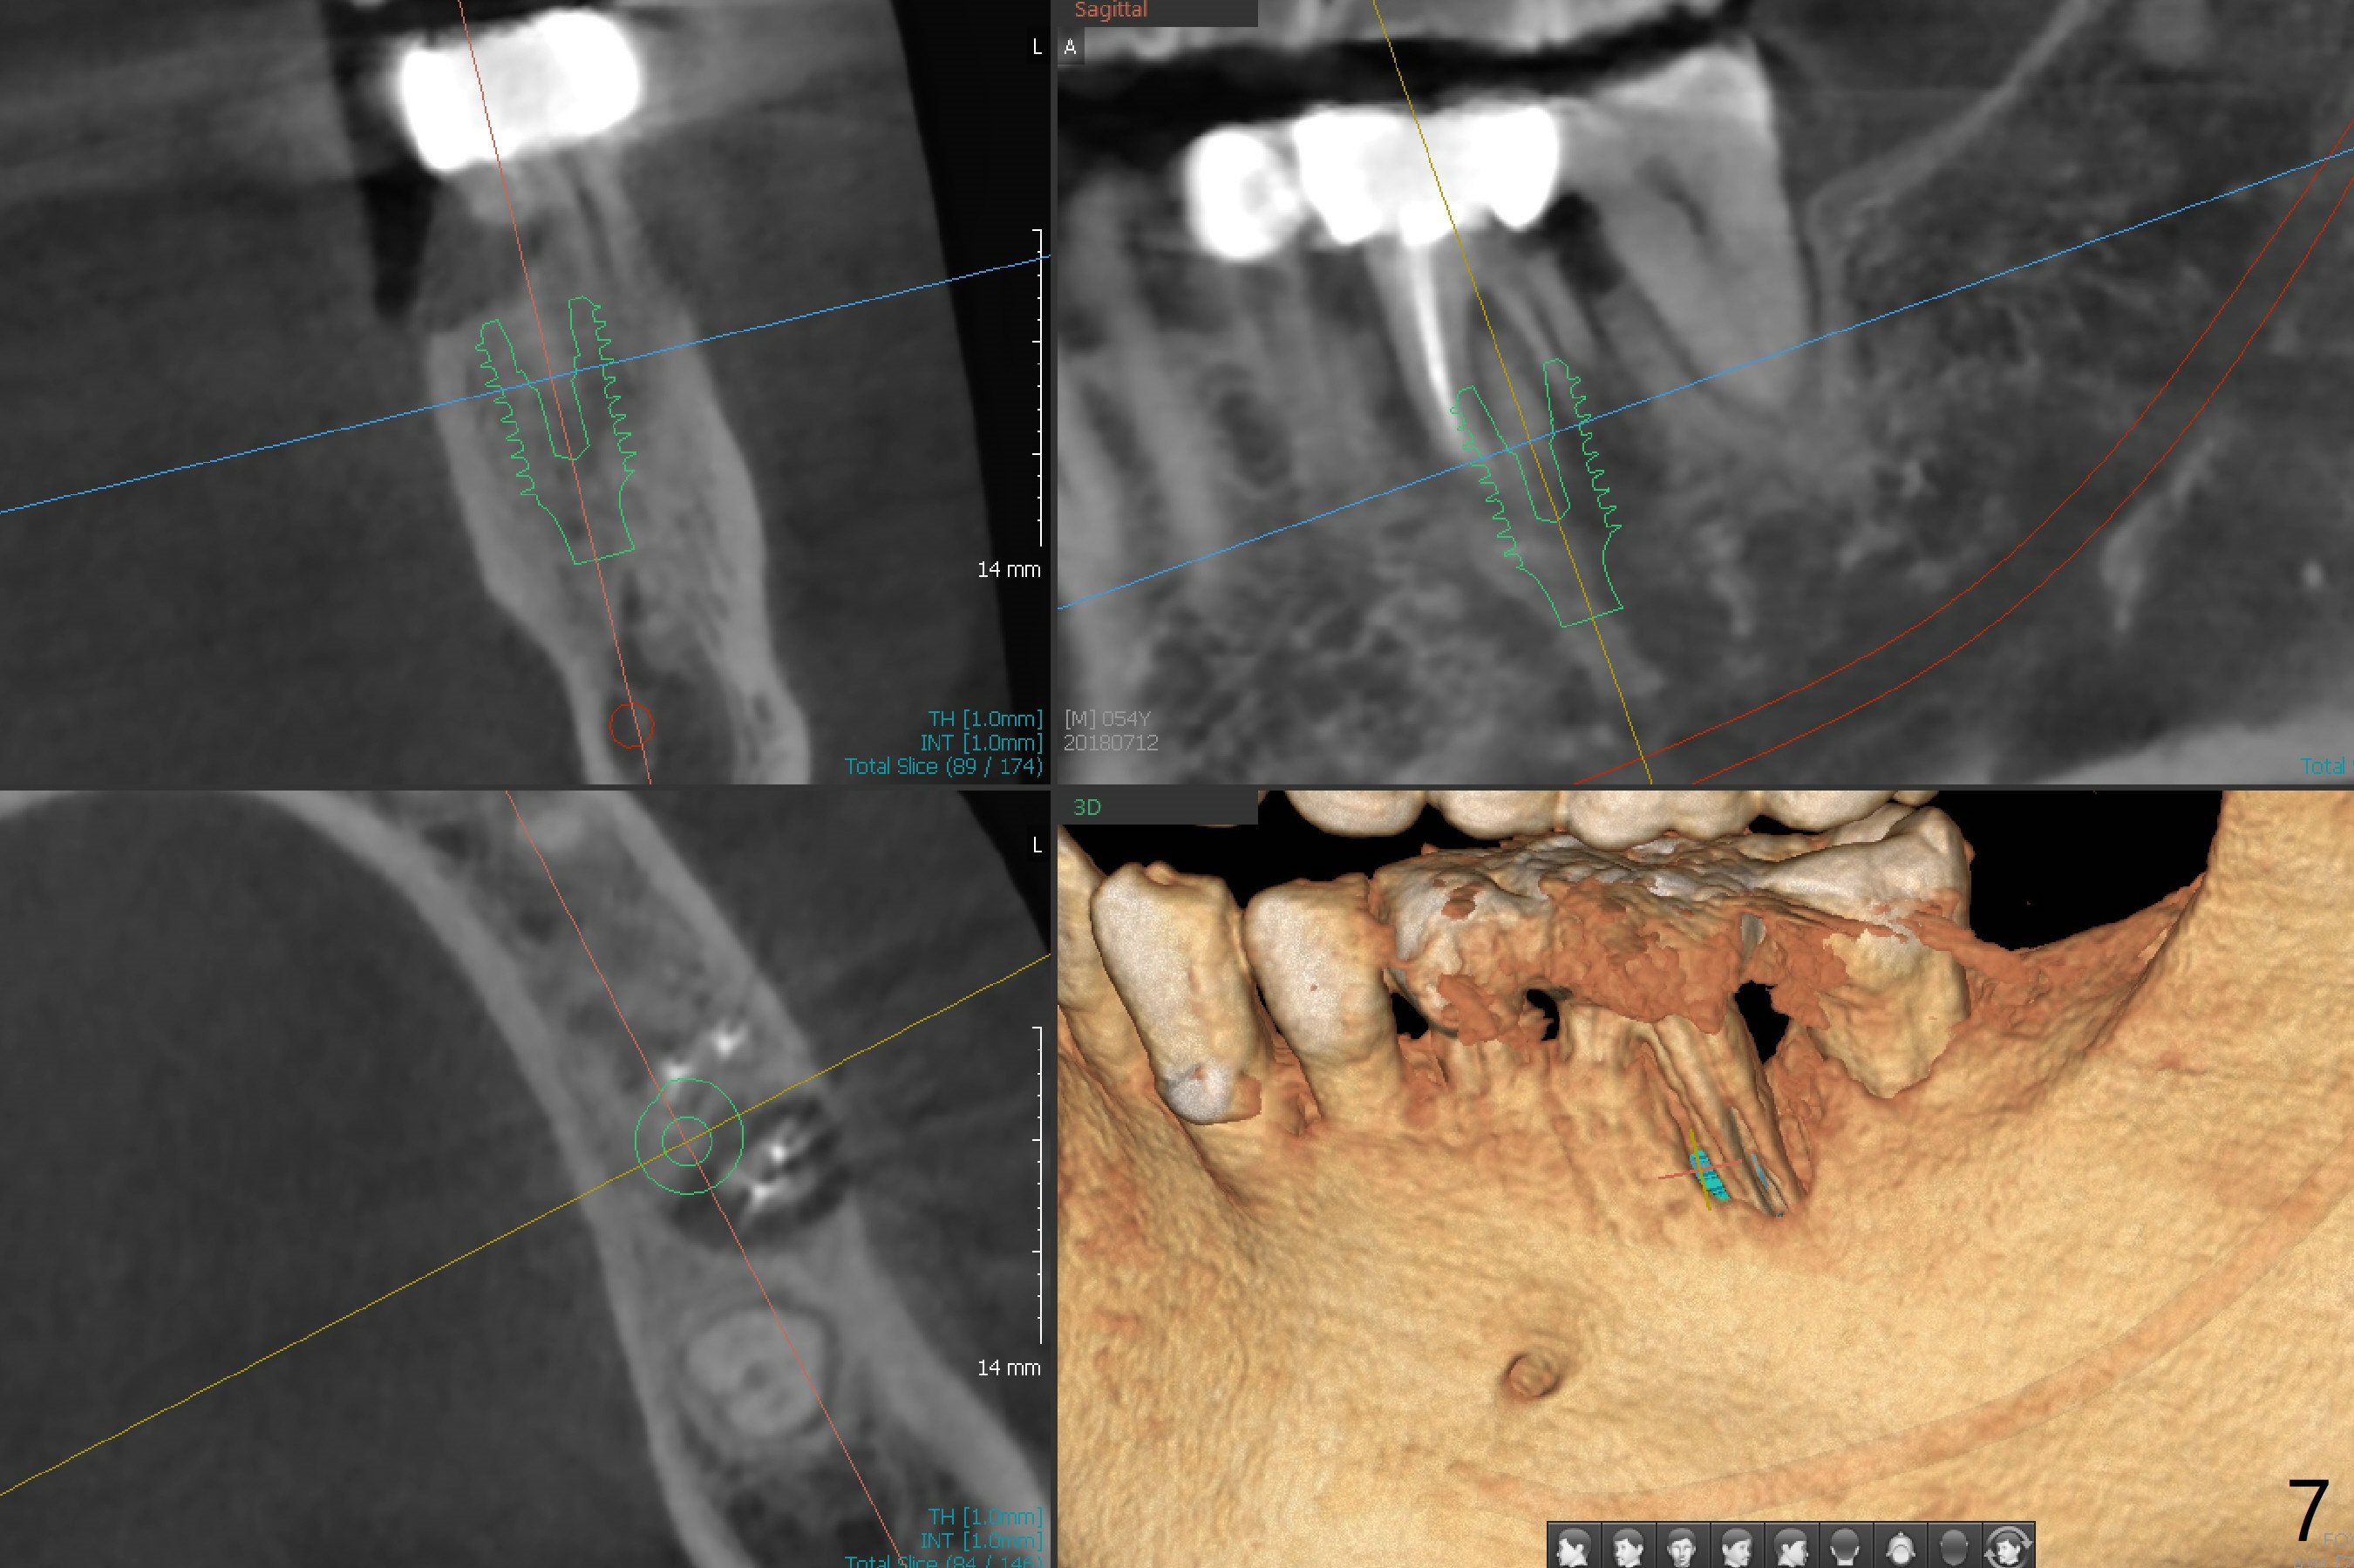

Distal Root Fracture

A 54-year-old man has distal (D) root fracture at #19 while the implant at #2 is osteointegrarting (Fig.1,2). Because of the large distal defect (Fig.3, after extraction), osteotomy (red line) will be initiated in the mesial socket (Fig.4, as distal as possible, with the coronal end in the middle of the socket) or the mesial slope of the septum (Fig.5) so that the implant (green) will be supported by the distally displaced septum (Fig.6 arrow). CT taken 8 months later confirms distal root fracture. A 6x11.5 mm or longer implant seems to be appropriate for the site (Fig.7). Three years later there is severe buccal swelling (Fig.8) with vertical mesial and distal root fractures (Fig.9). Although the buccal plate is lost, the septum remains (Fig.10 S), which will provide with blood supply to the bone graft (Fig.11), covered with Bioxclude and 6-month membrane and PSA suture. The bone density in the mesial and distal sockets is higher than that in the septum 8 months post cortical bone graft (Fig.12). In spite of bone graft, the buccolingual width reduces by almost 4 mm 8 months post extraction (Fig.3,4). In spite of bone graft, the buccolingual width reduces by almost 4 mm in 8 months post extraction (Fig.3,4). A 5x11.5 mm implant will be placed (Fig.15).